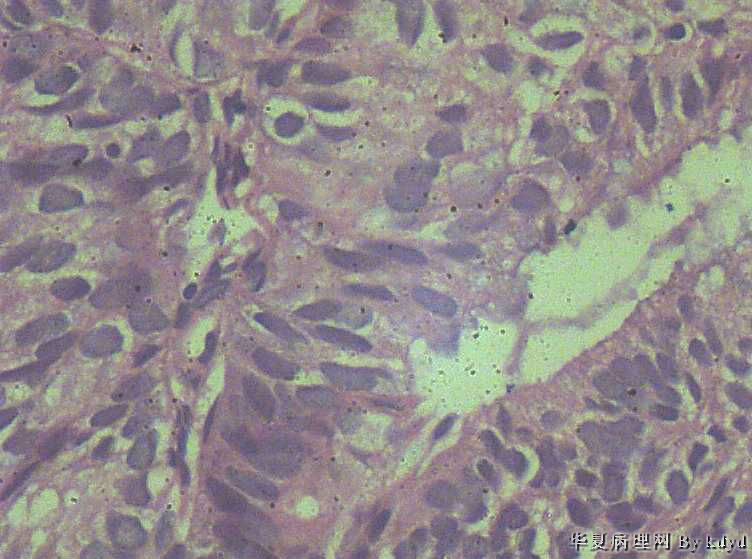

51岁,停经一年后,阴道流血。行宫腔诊刮。

疑问:1。腺体呈复杂性增生伴不典型增生?

2。腺体有分泌反应,有些腺体看上去又像是宫颈的腺体(手术医生说是宫腔取的)?

• 腺体非典型增生?是宫腔还是宫颈??图1

图1

• 腺体非典型增生?是宫腔还是宫颈??图2

腺体密集,有背靠背、共壁,有乳头状结构,有核异性性,有病理核分裂:

子宫内膜中-重度不典型增生,癌变不能排除

报了个 复杂性增生伴轻-中度不典型增生。 以跟医生交代了一下,叫病人最好 进一步检查 。

宫内膜间质消失,子宫内膜癌

现在回过头来看这个片子,又觉得够上癌了呢。

子宫内膜样癌

宫内膜样癌(高分化)。组织腺体拥挤、背靠背、血管纤维轴心乳头状,间质细胞消失代之纤维。

子宫内膜重度不典型增生,癌变。

子宫内膜样癌。

腺癌,内膜和宫颈的很难区分,可结合免疫组化,ER\PR,上色就应该是内膜来源,不上色就是宫颈了